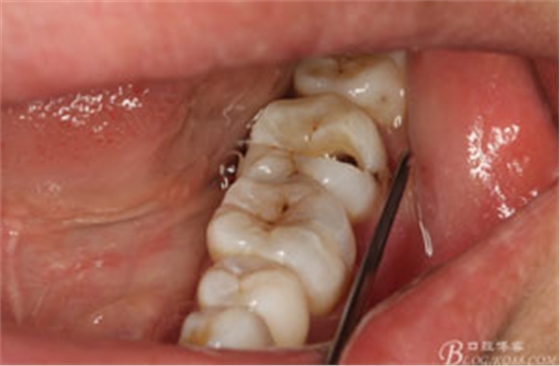

圖2.37牙冠基本完好,松動(dòng)Ⅰ度。合面有一開(kāi)髓孔被棉球覆蓋,頰側(cè)牙齦輕度紅腫。

圖3.取出棉球口內(nèi)發(fā)現(xiàn)37合面有開(kāi)髓孔,探針出血,頰側(cè)牙齦紅腫